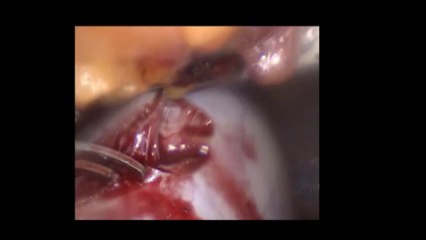

Laparoskopi ile Endometiroma (Çikolata kisti) operasyonu 1 - Prof. Dr. Aydan Biri

Laparoskopi ile Endometiroma (Çikolata kisti) operasyonu 1 - Prof. Dr.